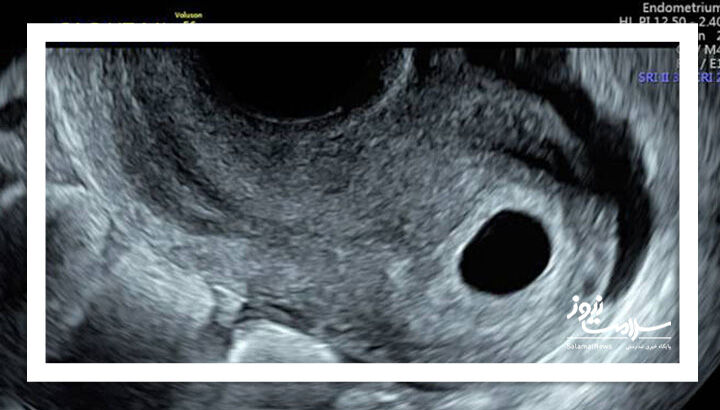

تشخیص قطعی بارداری پوچ تنها از طریق سونوگرافی امکانپذیر است که کیسه حاملگی خالی را نشان میدهد.

پزشک با استفاده از سونوگرافی ترانس واژینال، بارداری پوچ را تشخیص میدهد. این بررسی معمولاً بین هفتههای ۷ تا ۹ بارداری انجام میشود. در این مرحله، جنین باید در سونوگرافی قابل مشاهده باشد. در مواردی که بارداری پوچ وجود دارد، کیسه حاملگی خالی دیده میشود.